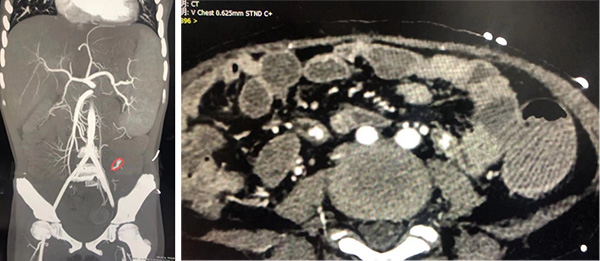

情况紧急,血液二科立刻请来重症医学科方伯梁主治医师、消化科梅天璐主治医师共同会诊,维持住小玲的生命体征。考虑患儿出血量大,内科手段已无法止血,不除外大血管破裂导致,需尽快明确出血灶。虽然是周末,影像中心孙记航医师了解情况后立即加急为小玲开辟绿色通道,紧急进行了增强CT检查,迅速发现小玲的肠道小动脉存在一个小裂口,正是这个小裂口让小玲出血不止。

病情刻不容缓,血液二科积极联系影像中心、麻醉科、手术室。影像中心阴捷副主任医师二话不说,匆忙从家中赶来,为小玲定下了手术方案,并紧急进行了介入手术。手术整整进行了近3个小时,阴捷副主任医师耐心细致,逐层寻找出血病灶,管床医生赵莎莎大夫全程陪伴患儿,因为有增强CT的精准定位,终于在蜘蛛网一样的肠道血管中找到了那条小动脉,动脉出血终于止住了。